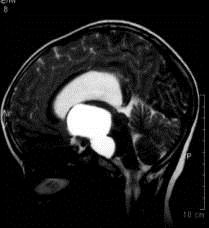

病历摘要:??患者女性,6岁,半年来感觉视力模糊,近10天出现反复头痛,间有恶心呕吐,精神转差,查体:神志清楚,身高90cm,体重25Kg,血压90/55...

问题 病历摘要:??患者女性,6岁,半年来感觉视力模糊,近10天出现反复头痛,间有恶心呕吐,精神转差,查体:神志清楚,身高90cm,体重25Kg,血压90/55mmHg,右眼视力4.6,左眼视力4.8,双侧视乳头水肿,颈软,伸舌居中,四肢肌张力正常,肌力5级,双侧Babinski征(-)。 患者术后第三天,病情加重,检查生化,血钠145mmol/l,尿比重1.010g/l,复查头部CT,发现右侧大脑中动脉供血区域密度减低,右侧脑室受压,蛛网膜下腔、脑室内少量积血,中线有移位,环池显示欠清,这时应采取的治疗措施有?